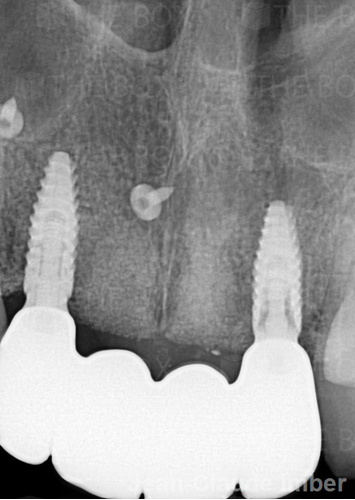

Infra bony defect one wall defect follow up 18 months show regeneration of buccal bone and interdental defect utilizing allograft bone substitute